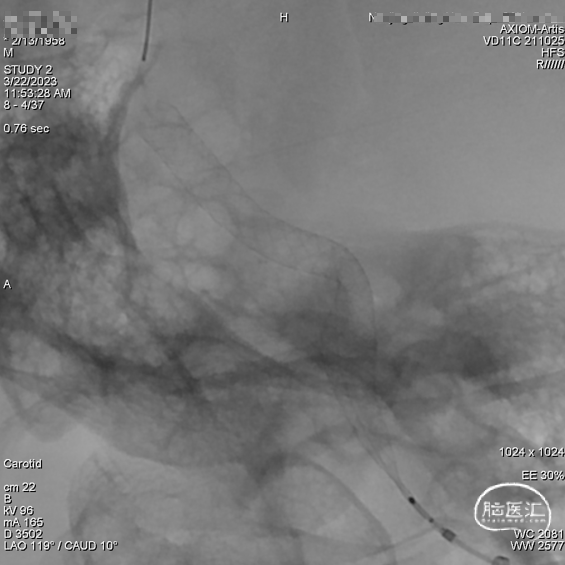

造影提示YonFlow®血流导向密网支架头端和后半段打开良好。

术后造影。

蒙片提示支架展开良好。

术后半年复查造影:YonFlow®血流导向密网支架贴壁良好,载流动脉前向血流良好。